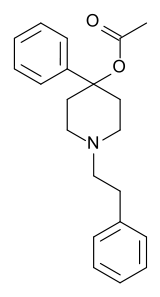

Phenylpiperidines

- Pethidine (meperidine)

- Ketobemidone

- MPPP

- Allylprodine

- Prodine

- PEPAP

- Promedol